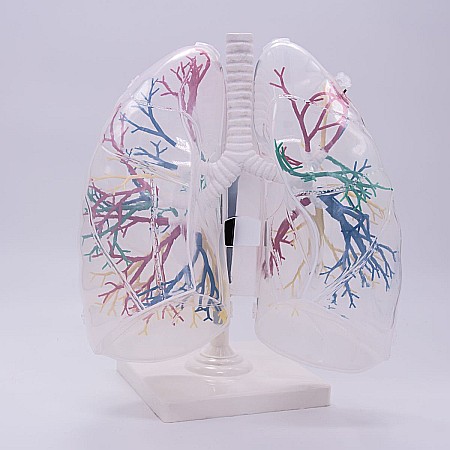

Modelul este conceput din material plastic PVC și este frumos colorat.

Acest model este conceput ca ajutor vizual pentru predarea cursurilor de anatomie umană și igienă. Este folosit pentru a demonstra structura dintelui, la studiul sistemului digestiv în gimnaziu, liceu și școli postliceale medicale.

Acest model are înălțimea de 23-26 cm, prezintă 3 rădăcini, o secțiune longitudinală prin care se poate observa structura interioara a dintelui, este conceput din material plastic PVC și este frumos colorat.